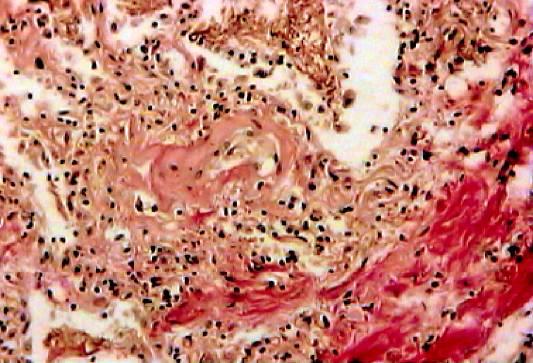

Карнификация Легкого: Микропрепараты и Диагностика

Раздел: Калейдоскоп образов